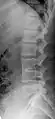

Congenital block vertebra in the lumbar spine (partial vertebrae 3 and 4). The rear portion of the disc still exists.